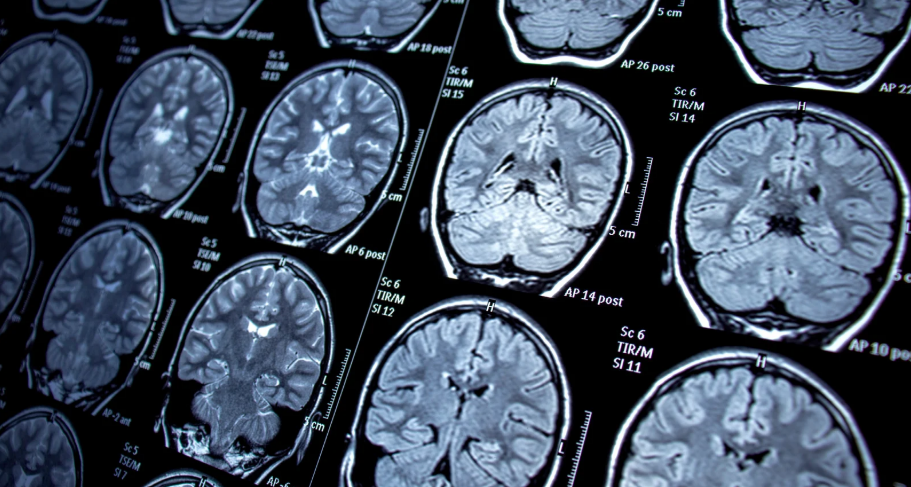

MRI 검사는 예상치 못한 사고나 질병으로 인해 필요할 때가 많습니다. 하지만 검사 비용이 상당히 부담될 수 있는데요. 실손의료보험(실비보험)을 통해 MRI 비용을 보장받을 수 있는 방법을 알아보고, 부위별 보장 차이와 실비보험 외 MRI를 보장하는 보험에 대해서도 살펴보겠습니다.

부위별 MRI 검사 비용 차이 & 건강보험 적용 여부

MRI 검사 비용은 건강보험 적용 여부에 따라 달라집니다.

✔️ 건강보험 적용 가능 (급여 항목)

- 뇌·뇌혈관, 특수검사, 두경부, 복부·흉부 검사 등

- 건강보험 적용으로 검사 비용이 절감됨

✔️ 건강보험 적용 불가 (비급여 항목)

- 교통사고, 디스크 의심, 허리·손목·무릎 검사 등

- 건강보험이 적용되지 않아 높은 검사 비용 발생

MRI 검사는 두통, 허리·무릎 통증, 디스크 등 다양한 이유로 필요하지만, 비용 부담이 큽니다.